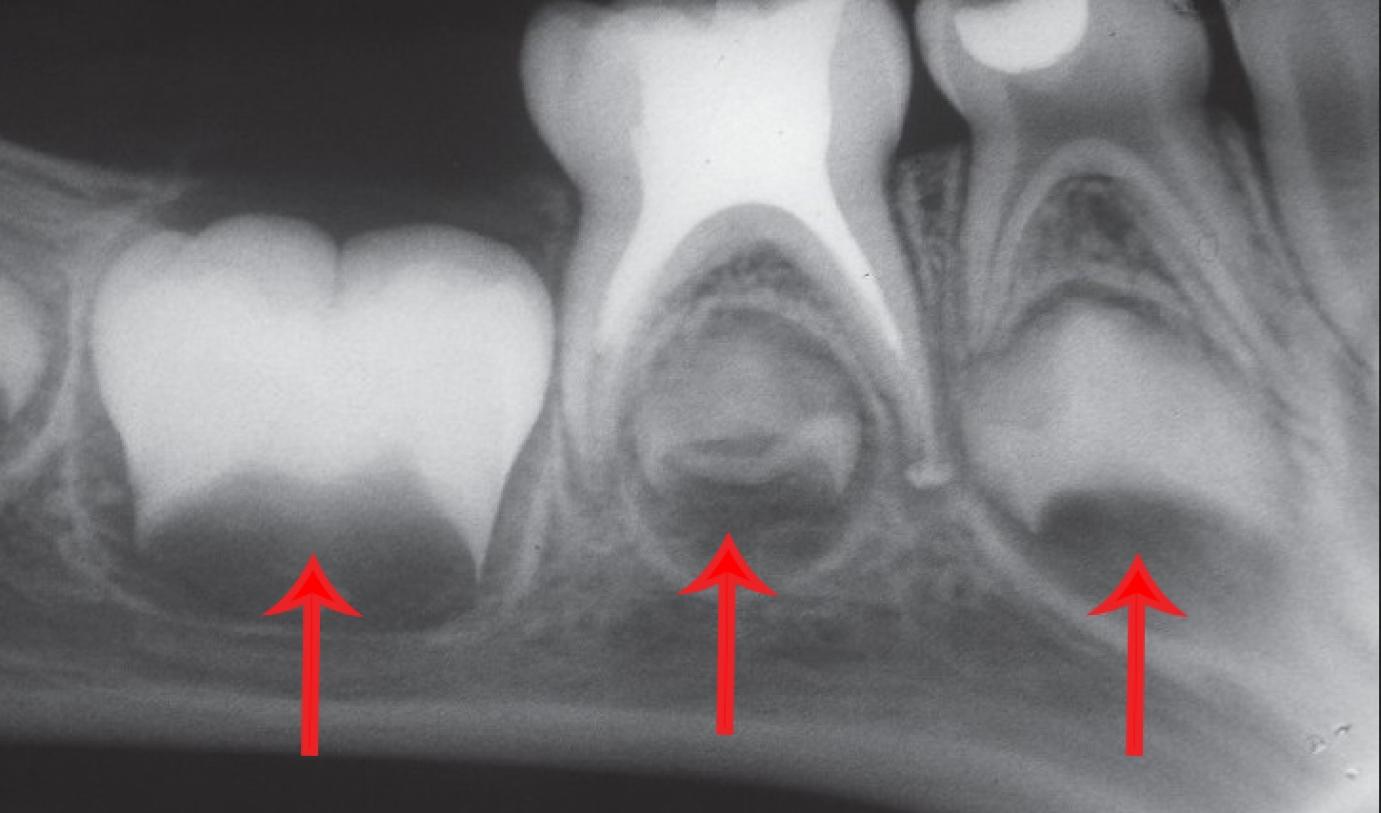

Fogcsíra

Fogcsírának nevezzük a fogakat (akár maradó fog, akár tejfog) azelőtt, mielőtt előtörnének (ezáltal csak röntgenfelvételen láthatóak az állcsontban). Ez jelenthet nagyon kezdetleges állapotot, amikor csak a koronának egy része fejlődött ki, de vonatkozhat későbbi stádiumra is, amikor már a gyökérnek egy része is kialakult. Nagyon fontos a fogszabályozás szempontjából, hogy a kezelés megkezdése előtt ellenőrizzük az összes maradófogat vagy azok csírájának meglétét!